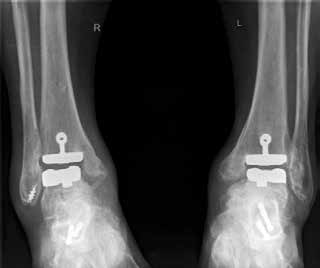

Arthrose stellt weltweit die häufigste Gelenkerkrankung dar und hat damit einen wesentlichen sozioökomischen Einfluss 1. Während 15 % der weltweiten erwachsenen Bevölkerung von Arthrose betroffen sind 2, leiden lediglich 1 % der Bevölkerung 3 bzw. 4,4 % der Arthrosepatienten 4 an einer Arthrose des oberen Sprunggelenks (OSG). Circa 80 % der Arthrosen des OSG sind ursächlich als posttraumatisch einzustufen, nur 9 % gelten als primäre Arthrosen. Dies unterscheidet die Arthrose des OSG von Coxarthrose (58 % primär) und Gonarthrose (67 % primär). 13 % treten im Rahmen systemischer Erkrankungen wie rheumatoider Arthritis, Hämochromatose, Hämophilie oder Osteonekrose auf 5 6. Die posttraumatische Arthrose des OSG wird besonders nach in Achsabweichung verheilten Frakturen (Pilon-tibiale-Frakturen, Weber-A‑, ‑B- und ‑C-Frakturen; Abb. 1a), Bandinstabilitäten des lateralen und medialen Bandapparates des OSG (Lig. fibulotalare anterius, Lig. fibulocalcaneare, Lig. fibulotibiale posterius etc.), nach rezidivierenden ligamentären Verletzungen sowie nach Gelenkverletzungen mit Knorpelschaden, „flake fractures“ oder „bone bruise“ beobachtet 7. Daher ist bei den vergleichsweise häufigen Weber-B- und ‑C-Frakturen die osteosynthetische Versorgung mittels Drittelrohrplatte und Zugschraube (Abb. 1b) sowie ggf. Syndesmosennaht mit Implantation einer Stellschraube mit millimetergenauer Reposition essentiell, um langfristig die Funktionsfähigkeit des OSG aufrechtzuerhalten und eine frühzeitige posttraumatische Arthrose zu verhindern 8.

Endoprothetik des OSG

Die Indikation zur endoprothetischen Versorgung einer OSG-Arthrose ist gründlich zu stellen. Darunter fällt die schwere Arthrose jeglicher Ätiologie mit täglich intensiven Schmerzen, hochgradigem Gelenkfunktionsverlust und Gelenkdestruktion. Voraussetzungen sind eine gute Knochenqualität sowie mittleres Alter ohne schwere systemische Vorerkrankungen. Auch bei der Implantation von Endoprothesen des oberen Sprunggelenkes ist es wichtig, bestehende Achsfehlstellungen entweder in gleicher Sitzung oder zuvor zu korrigieren. Sofern nach Achskorrektur die Versorgung mittels einer Endoprothese noch notwendig ist, soll damit die Funktionsfähigkeit des Gelenks, eine Schmerzeliminierung und eine Verbesserung der Lebensqualität erreicht werden (Abb. 6). Kontraindikationen sind neben den bereits oben genannten: bestehende Osteonekrosen, periphere arterielle Verschlusskrankheit, periphere Neuropathie, bestehende oder stattgehabte Gelenkinfektion und schwere Bandinstabilität 56.

Im Vergleich zur Endoprothetik des Hüft- und Kniegelenks bestehen höhere Komplikationsraten bei der Endoprothese des Sprunggelenks. Intraoperativ sind dies meist operationstechnische Komplikationen bei der Osteotomie der Malleoli, beim Sägen oder beim Positionieren der Prothesenkomponenten 57. Postoperativ sind dies vornehmlich Wunddehiszenzen und Infektionen 58, während im Langzeitergebnis aseptische Prothesenlockerung, periprothetische Stressfrakturen und Retraktion der Gelenkkapsel sowie der periartikulären Weichteile auftreten 59.